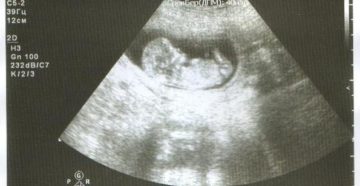

Отслойка плодного яйца на ранних сроках беременности: деформация гематома Плодное яйцо обнаруживают на УЗИ в…